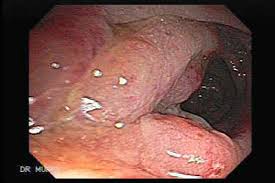

Understanding Diverticulosis And Diverticulitis Saint Luke S Health System from api.kramesstaywell.com The most frequent issues with the bowel or colon, affect the colon's ability to work properly. Diverticulitis involves common digestive tract growths called diverticula. In the retrospective part of the study, 27 patients were diagnosed with diverticulitis and 31 were diagnosed with colon cancer. infographic diverticulitis, an intestinal disorder marked by serious symptoms, is often misdiagnosed as colon cancer. Another condition that can be misdiagnosed as cancer in the colon is hemorrhoids. Considering the ambiguity of these symptoms, it's not surprising that colon cancer is often misdiagnosed as a benign case of diverticulitis. Changes in stool or bowel movement may be suggestive of colon cancer—particularly if you have risk factors for the disease—but there are numerous other explanations for these symptoms. The findings most specific for diverticulitis were pericolonic.

Diverticulosis is a condition that describes small pouches (diverticula) in the wall of the digestive tract that occur when the inner layer of the digestive tract bulges through weak spots in the outer layer. Colon cancer however is caused by small lumps that progress into cancerous tumors. infographic diverticulitis, an intestinal disorder marked by serious symptoms, is often misdiagnosed as colon cancer. The diagnosis of cancer was made within 6 months from the date. Also called colorectal cancer, it often has no noticeable symptoms until late. Although at first diverticulitis and colon cancer may present similar symptoms, they are two very different conditions. 1 doctor answer • 1 doctor weighed in i did a ct scan came back negative for diverticulitis but showed a narrowing of the colon. (diverticulitis, appendicitis, colon cancer, chronic inflammatory disease of the intestine) should be sought for any. Diverticulitis is a condition set off by infection or rupture of diverticula,. So, the physician has to make a clinical diagnosis of diverticulitis. The most frequent issues with the bowel or colon, affect the colon's ability to work properly. Colon cancer may of course present with similar symptoms including abdominal pain, diarrhea (if there is an obstructing lesion) and rectal bleeding but colonoscopic findings usually assist in separating these diagnoses. When these diverticula become inflamed or infected, diverticulitis can develop.

Colon polyps are growths on the inner lining of the colon, and diverticulitis happens when a diverticulum ruptures and becomes infected. If left untreated, diverticulitis can lead to a collection of pus outside the colon wall or a generalized infection in the lining of the abdominal cavity, a condition known as peritonitis. In many cases, patients with colon cancer have been diagnosed with inflammatory bowel diseases such as ibs, colitis, and diverticulitis. Another condition that can be misdiagnosed as cancer in the colon is hemorrhoids. Most times it occurs when small pouches called diverticula become infected or swollen. The most frequent issues with the bowel or colon, affect the colon's ability to work properly. August 8, 2009 at 12:09 pm. Usually a ct scan is needed to diagnose an abscess, and treatment usually requires a hospital stay, antibiotics applied through a vein and possibly drainage. The findings most specific for diverticulitis were pericolonic. When these diverticula become inflamed or infected, diverticulitis can develop. Colon cancer may of course present with similar symptoms including abdominal pain, diarrhea (if there is an obstructing lesion) and rectal bleeding but colonoscopic findings usually assist in separating these diagnoses. Irritable bowel syndrome (ibs) is a chronic gastrointestinal disorder. In the retrospective part of the study, 27 patients were diagnosed with diverticulitis and 31 were diagnosed with colon cancer.

When these diverticula become inflamed or infected, diverticulitis can develop. Also called colorectal cancer, it often has no noticeable symptoms until late. Helical ct scans of 40 patients admitted to the er with the clinical diagnosis of diverticulitis and 14 patients diagnosed with colon cancer were retrospectively reviewed. Colon issues 4 years, 4 ct scans over 4 years show diverticulosis, sigmoidoscopy to 35cm normal, woke to bloody diaherea today colon cancer? The most frequent issues with the bowel or colon, affect the colon's ability to work properly. Hi, please can anyone help me, am in so much pain. These conditions are far more common but can mimic many of the signs and symptoms of colon cancer. 1 doctor answer • 1 doctor weighed in i did a ct scan came back negative for diverticulitis but showed a narrowing of the colon. Diverticulitis involves common digestive tract growths called diverticula. I was diagnosed with diverticulitis with a severe infection; Conditions that mimic colon cancer. It was just suppose to be a routine ct scan before a surgery. No, as stated above, there are quite a few similarities between diverticulitis and colon cancer starting from the symptoms, which is acute abdominal pain or rectal bleeding, but while diverticulitis is caused due to inflammation of the diverticuli where as the colon cancer develops from entirely different factors.